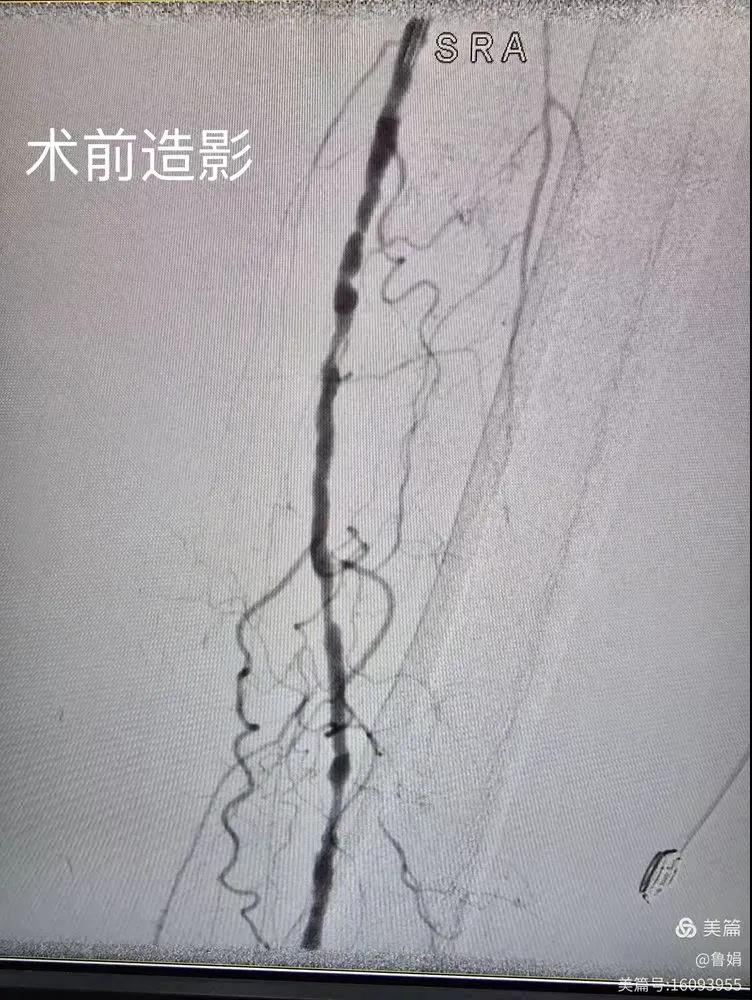

據(jù)悉,該患者,女,73歲,下肢動(dòng)脈硬化閉塞癥,“以靜息痛,間歇性跛行”入院,CTA評(píng)估:股淺動(dòng)脈,腘動(dòng)脈間斷性多段重度狹窄,外二科血管外科團(tuán)隊(duì)根據(jù)患者病情,結(jié)合檢查結(jié)果,經(jīng)過(guò)科室會(huì)診后,決定對(duì)該病人行介入治療。手術(shù)由周創(chuàng)業(yè)副主任與北大一院血管外科專家郭宏杰教授聯(lián)合開(kāi)展,對(duì)股淺動(dòng)脈,腘動(dòng)脈重度閉塞段行血管開(kāi)通+藥涂球囊擴(kuò)張成形,術(shù)后狹窄明顯緩解,血流恢復(fù)!